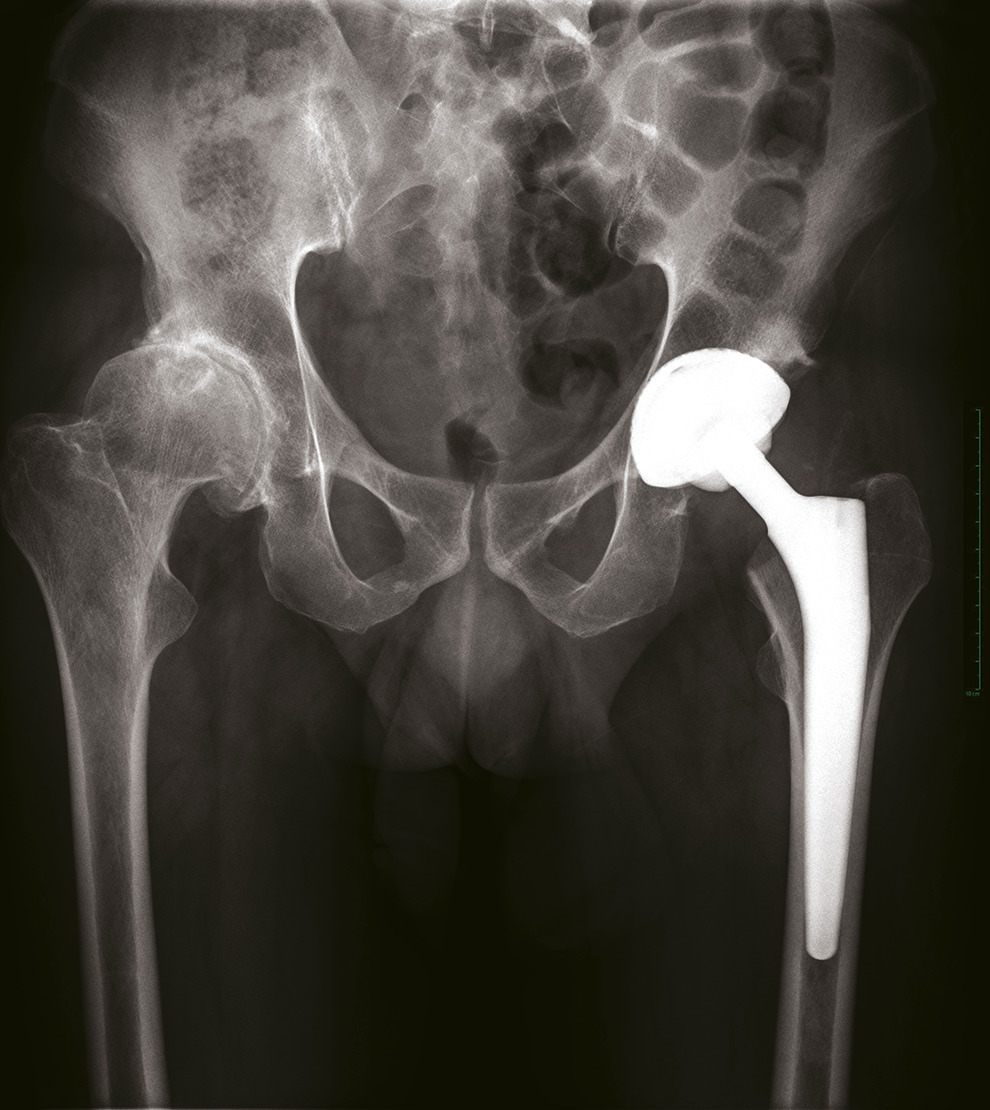

Diagnostic radiologique

Le bilan radiographique comprend des clichés en charge : bassin de face et faux profil de Lequesne. Les radiographies permettent de confirmer le diagnostic (pincement articulaire, géodes et ostéophytes) [fig. 3 ]. Elles permettent de rechercher une anomalie architecturale sous-jacente (dysplasie, séquelle de maladie de l’enfance). En cas de doute diagnostique ou en cas de pathologies intriquées (rachis : cruralgie-coxarthrose), un test à la xylocaïne peut être réalisé. Ce test consiste à injecter quelques millilitres de xylocaïne à 2 % au niveau de l’articulation coxo-fémorale. La disparition de la douleur dans le quart d’heure qui suit la procédure signe la responsabilité de la hanche dans les douleurs du patient ; ce test permet de prédire le résultat que le patient pourrait espérer d’une arthroplastie totale de hanche.

L’arthroplastie totale de hanche, c’est-à-dire l’implantation d’une prothèse totale de la hanche, est le traitement de référence de la coxarthrose invalidante, une fois le traitement médical dépassé. Chaque année, environ un million de prothèses sont implantées dans le monde chez des patients atteints de coxarthrose.1 La longévité des prothèses de la hanche a été démontrée : leur survie à 10 ans est de 95 %. Dans certaines populations en bonne santé physique, où le patient a la capacité de faire de l’exercice, reste actif et maintient un poids normal, plus de 80 % des prothèses peuvent rester fonctionnelles à 25 ans.10